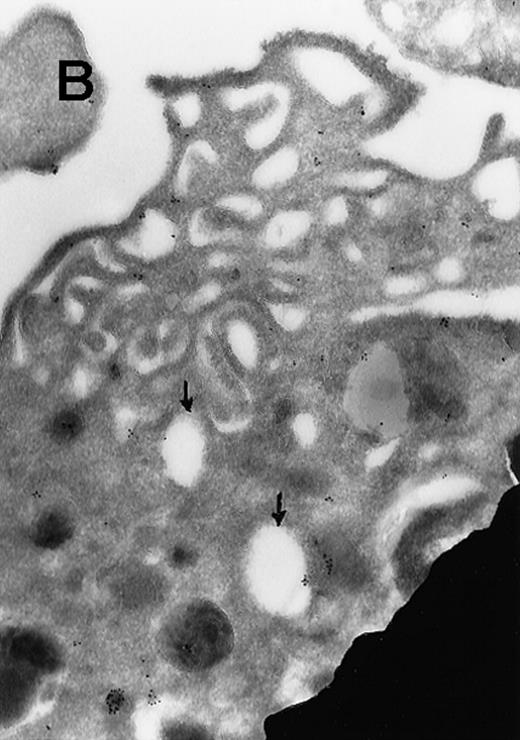

Immunogold Electron Microscopic assays (performed as described before)9.

(A) Ultrathin frozen sections of rat platelets immunolabeled with antibodies to ERK (magnification ×45 000). (B) Well-developed demarcation membranes in a rat (Wistar), TPO-treated megakaryocyte7 9 immunostained with an antibody to Mst1 (magnification ×48 000), or (C) with an antibody to ERK, which recognizes ERK1 and ERK2 (magnification ×65 400). The arrows point to the demarcation membranes. The Mst1 antiserum (gift of Dr Jonathan Chernoff, Fox Chase Cancer Center, Philadelphia, PA) and anti-ERK2 (K-23) (Santa Cruz Biotechnology, Santa Cruz, CA) or TR2, anti-ERK (gift of Michael Weber, University of Virginia Medical School) were diluted 1:10.

In view of these reports, we determined the cellular localization of MAP kinase in megakaryocytes, with a particular attention to the platelet-yielding demarcation membranes.7As a control, we determined the localization of another TPO-upregulated serine/threonine kinase, Mst1.8 Our current Electron Microscopic (EM) studies, performed as we described before,9 reveal that a significant fraction of MAP kinase, but none of Mst1, localizes to the demarcation membranes. In resting platelets, MAP kinase is found in a cluster pattern associated with the plasma membrane (which is believed to originate from the megakaryocytic demarcation membranes),7 as well as over electron-dense cytoplasmic domains (Figure). In view of our finding that MAP kinase is localized to the demarcation membranes in megakaryocytes, it is of interest to note that this kinase was also shown to be localized in Golgi membranes and involved in their fragmentation during mitosis in a microtubule-dependent manner.10 Platelet fragmentation likely involves the cytoskeleton, and perhaps MAP kinases are also involved in this process.